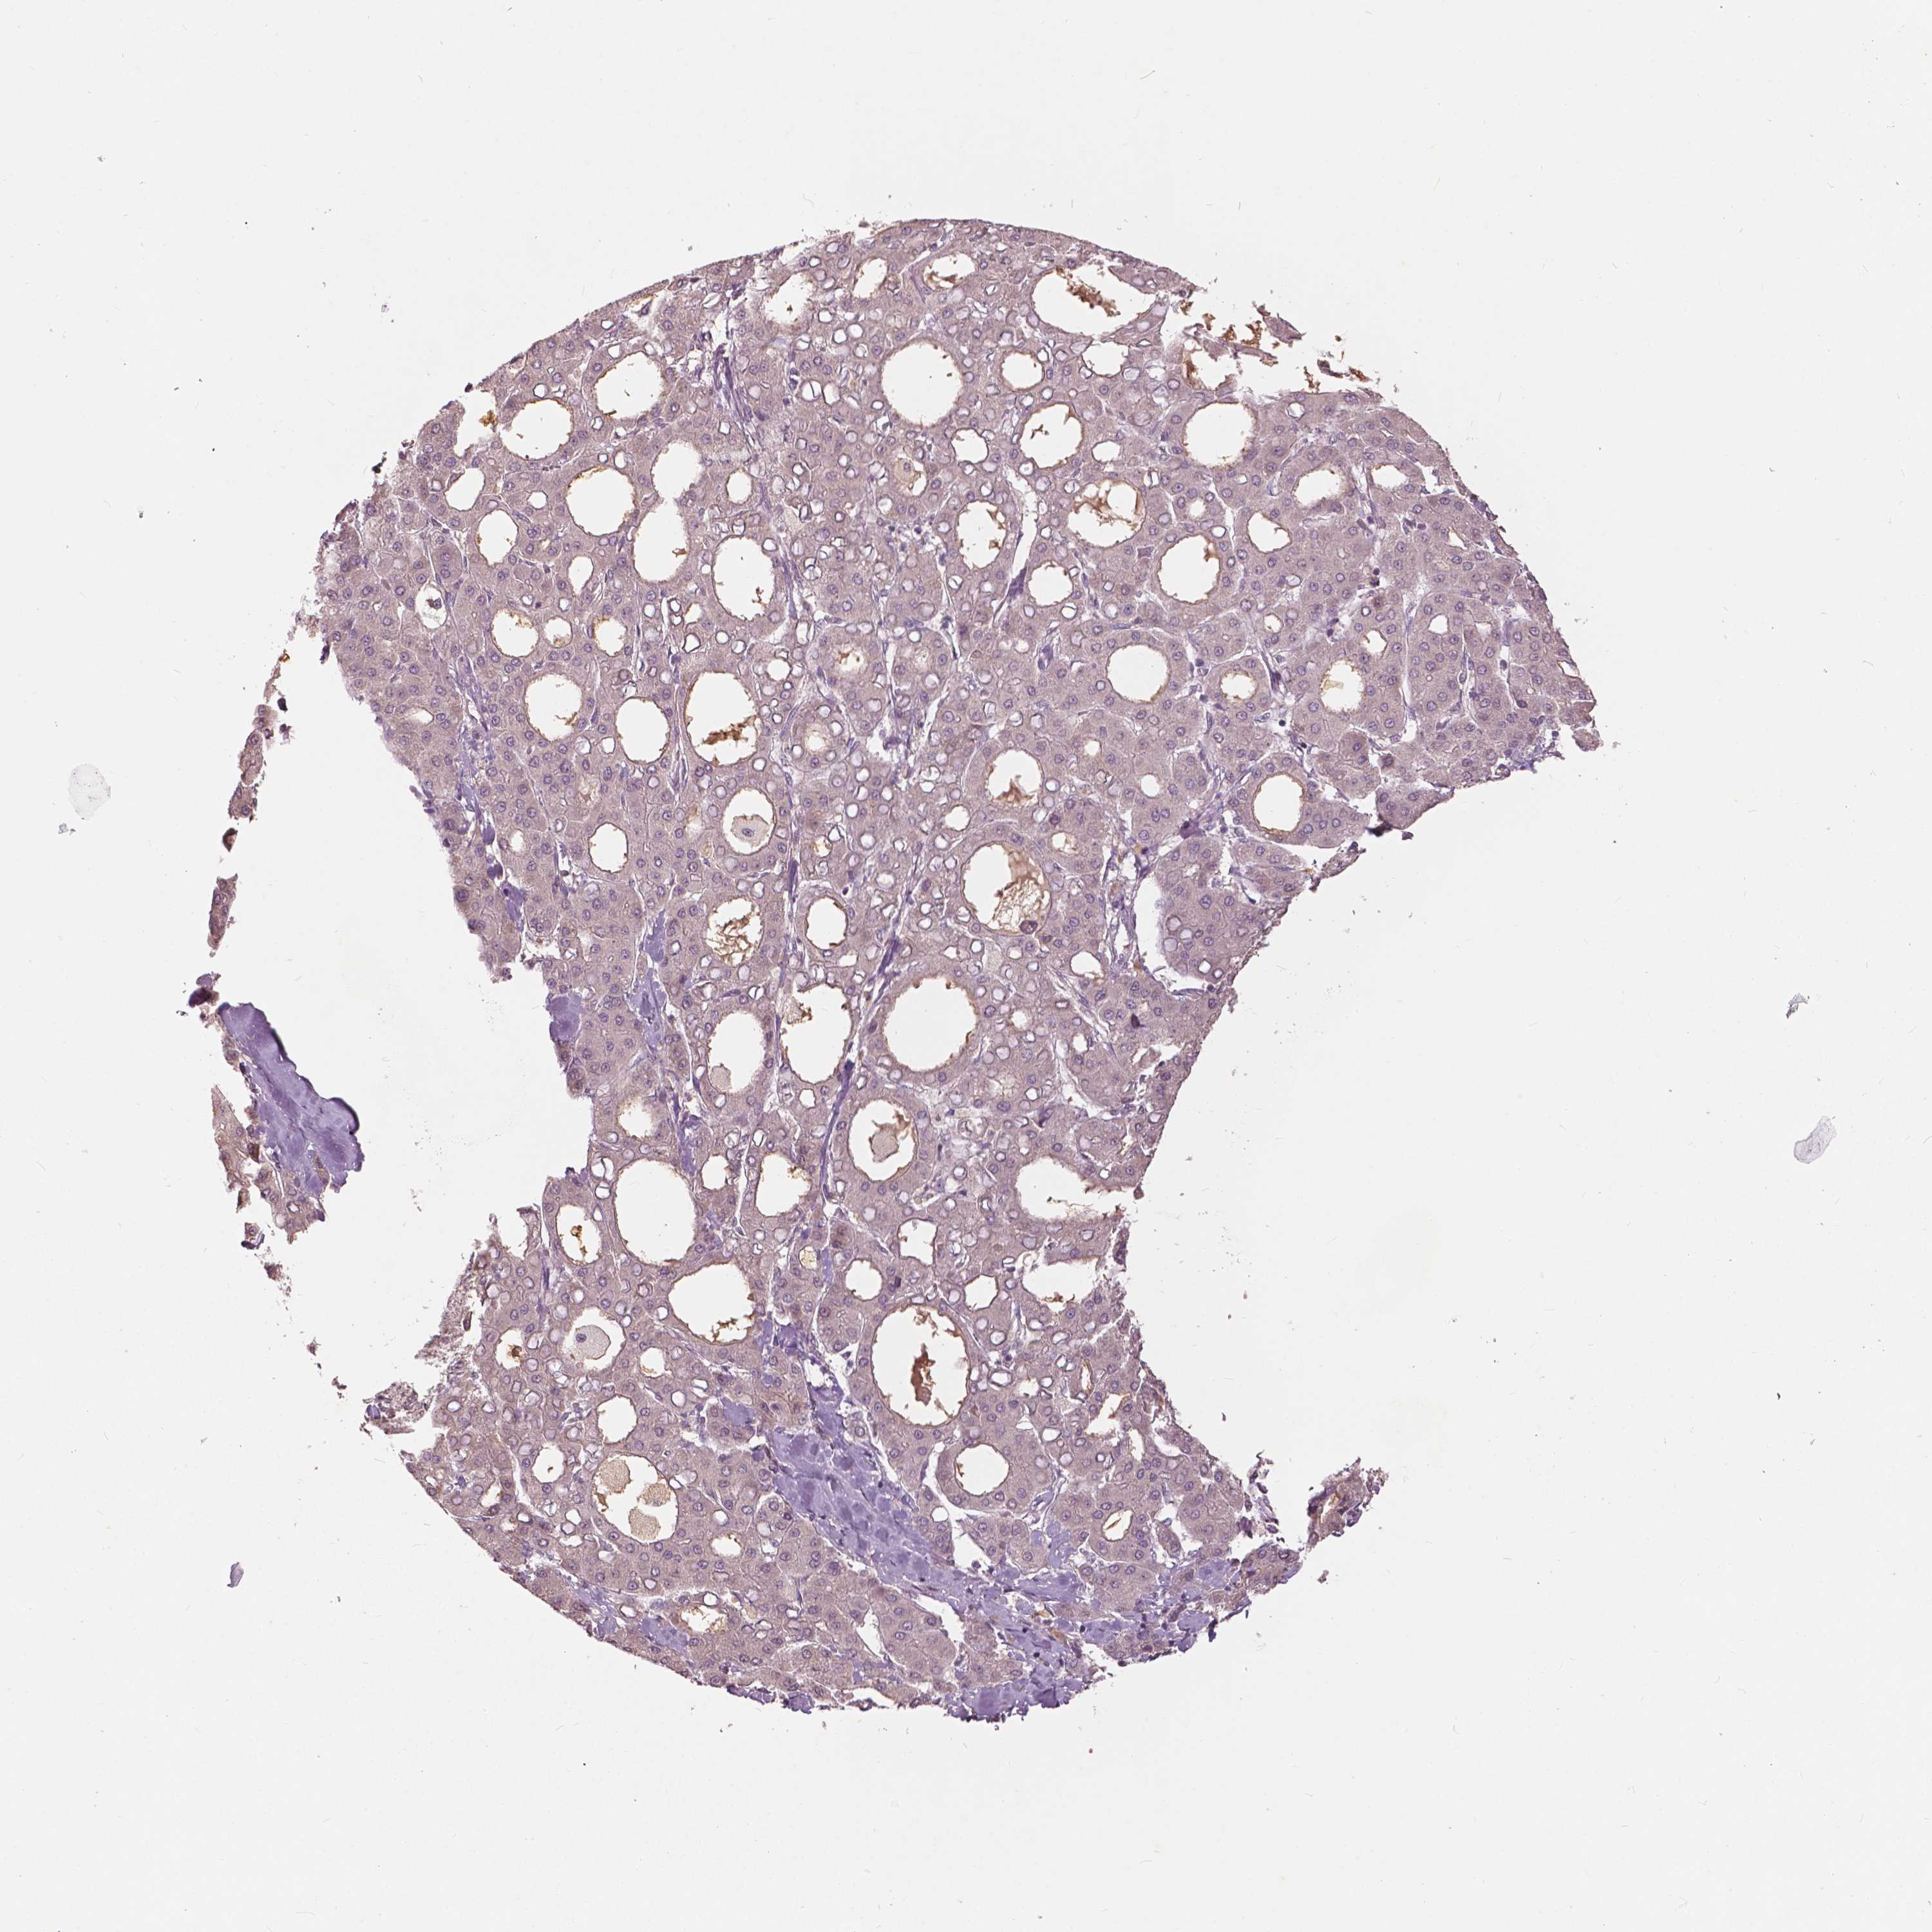

LIVER CANCER - Protein expressioni

A mouse-over function shows sample information and annotation data. Click on an image to view it in a full screen mode. Samples can be filtered based on level of antibody staining by selecting one or several of the following categories: high, medium, low and not detected. The assay and annotation is described here.

Note that samples used for immunohistochemistry by the Human Protein Atlas do not correspond to samples in the TCGA dataset.

Antibody stainingi

Antibody staining in the annotated cell types in the current human tissue is reported as not detected, low, medium, or high, based on conventional immunohistochemistry profiling in selected tissues. This score is based on the combination of the staining intensity and fraction of stained cells.

Each image is clickable and will lead to virtual microscopy that enables deeper exploration of all samples and also displays staining intensity scores, fraction scores and subcellular localization as well as patient and tissue information for each sample.

Antibody CAB033770

Staining

High

Medium

Low

Not detected

Intensity

Strong

Moderate

Weak

Negative

Quantity

>75%

75%-25%

<25%

None

Location

Nuclear

Cytoplasmic/membranous

Cytoplasmic/membranous,nuclear

Carcinoma, Hepatocellular, NOS

Cholangiocarcinoma